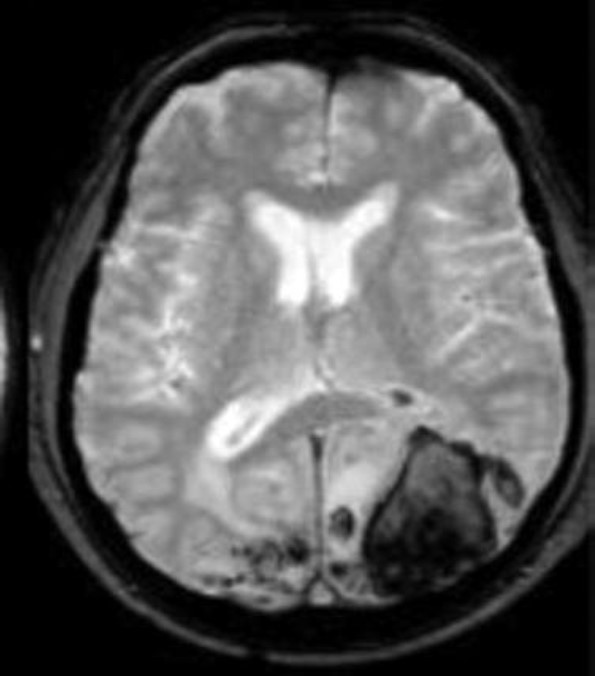

Question: An 83-year-old man with cognitive decline presents with altered mental status. The patients vital signs are normal and there has been no recent illness or fever. His laboratory tests (including coagulation profiles) are largely unremarkable and show no electrolyte abnormalities or infection. Which of the following is the most likely cause of the finding shown?

Correct Answer: Cerebral amyloid angiopathy

Explaination: The findings shown on this gradient echo sequence on magnetic resonance imaging (MRI) are consistent with cerebral amyloid angiopathy (CAA). CAA is a condition in which amyloid deposits in the media and adventitia of small and medium vessels. Although microhemorrhages are often seen on MRI, patients are often at increased risk of lobar hemorrhages. The risk of cerebral hemorrhage with either anticoagulation or antiplatelet agents is increased in this population. Caution must also be taken when using statins in this population, due to a slightly higher risk of bleeding. Chronic hypertension usually leads to bleeding in deepstructures of the brain such as the pons, basal ganglia, thalamus, or cerebellum. An AVM can be identified on this sequence on MRI, but usually shows a conglomeration of arteries and veins rather than small microhemorrhages. A subarachnoid hemorrhage usually follows the cortical convexity in the leptomeningeal space. A traumatic brain injury may result in contusion from a coup/contrecoup injury but usually is not associated with microhemorrhages.